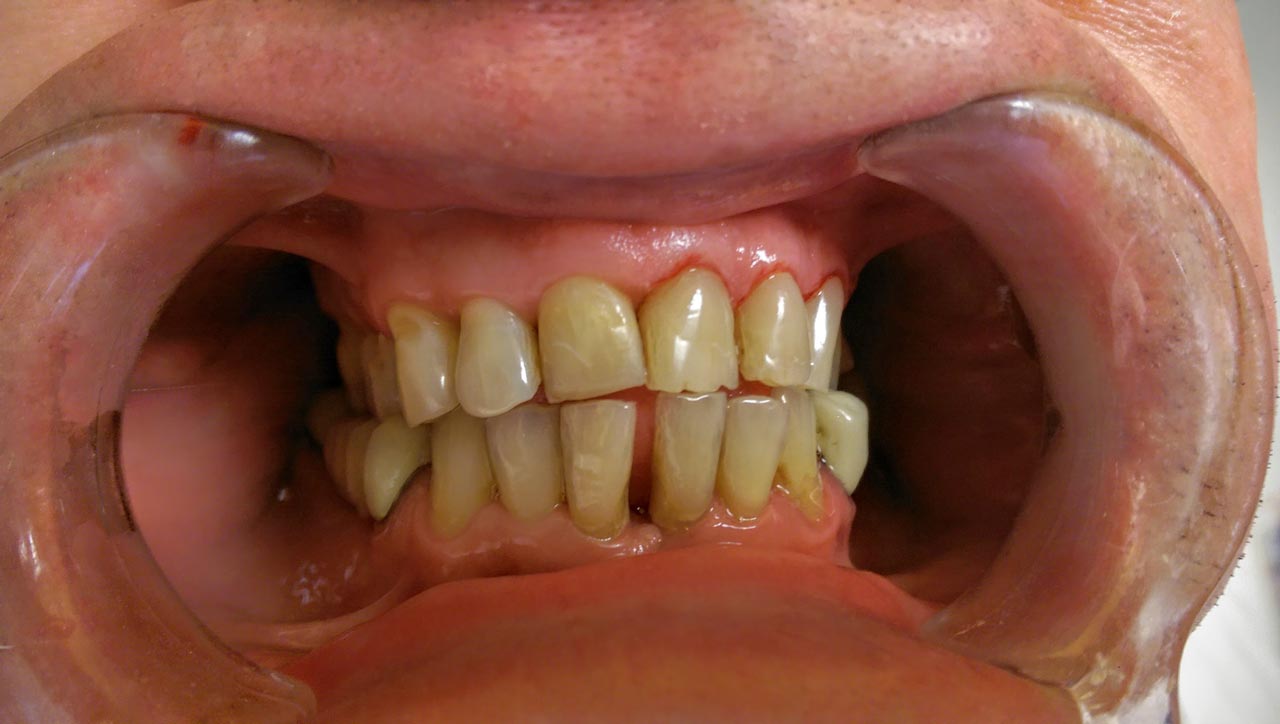

Alsó állcsont teljes rehabilitációja 72 óra alatt, azonnal terhelhető implantátumokkal súlyos paradontitisben szenvedő dohányzó páciens esetében. Az alsó állcsont fogai mind mozogtak az előrehaladott fogágypusztulás miatt.

A fogakat eltávolítottuk, a gyulladt, fertőzött csontot kitakarítottuk, kifertőtlenítettük, majd azonnal implantáltunk.

Svájci, IHDE márkájú, azonnal terhelhető implantátumokat helyzetünk be, és ezekre harmadnapra rögzített, hosszútávú, fémvázas, esztétikus műanyaggal leplezett hidat ragasztottunk be.

Ezt az ideiglenes hidat a sebek gyógyulása miatt használjuk, de tartóssága miatt véglegesként is használható. A legtöbb esetben, ahogy itt is, 6 hónap múlva porcelán hídra cseréljük, a teljes gyógyulás után.